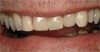

Figure  5  Loss of tooth surface and yellowing of teeth in a young patient with untreated GERD.

Figure 5

Characteristics of damage to tooth structures caused by acidity include wear on the occlusal surfaces of molars and a saucer shape on the cusps of molars (perimolysis).12 The erosion can vary from minor and subtle changes on the tooth surface, ie, loss of luster, a dull or matted look, to cupping on occlusal surfaces or incisal edges, which may extend to dentin. Usually, the erosive lesions demonstrate greater width than depth. When combined with abrasive forces or stresses, the tooth surface loss may occur at a faster rate (Figure 2, Figure 3, Figure 4 and Figure 5).